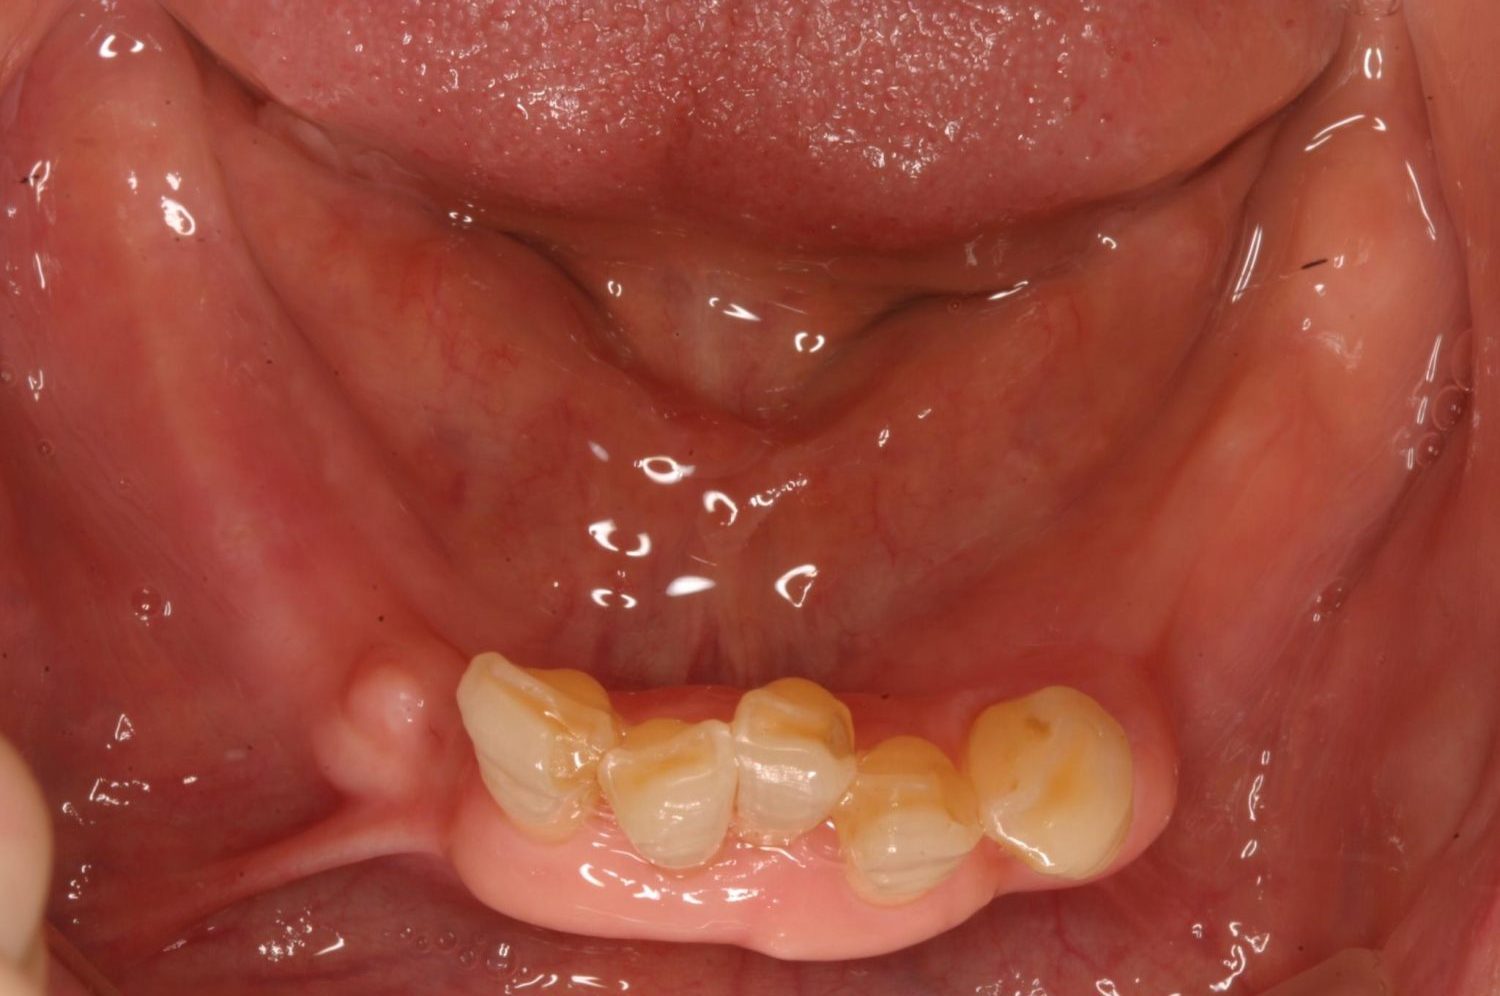

インプラント治療の症例紹介③

Before

After

主訴

むし歯の治療

治療内容

保存不可能な歯の抜歯

下顎にインプラント埋入し咬合再構成

治療費

2,688,400円(税込)

治療期間

14か月

治療回数

21回

想定されたリスク

※上部構造の形態が複雑になるため清掃が難しくなる。インプラント周囲炎の恐れがありました。

多数歯う蝕および多数歯欠損による咬合崩壊、保存不可能な歯の抜歯により上下無歯顎に。下顎に6本インプラント埋入する事で咬合再構成を行った。